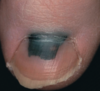

35

Mélanonychie

Mélanome unguéal